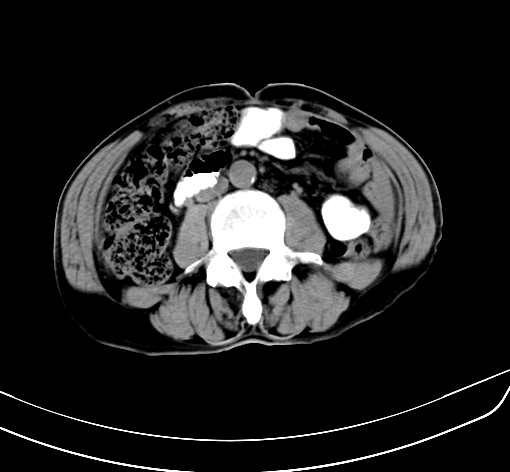

病人 男 70 咳嗽 胃部不适 2月余

胆囊壁增厚,与临近肝实质边界不清,临近肝实质内可见大片边界不清之低密度区,肝门区密度亦有减低,部分结构不清,尾叶前方可见块状影,肝右叶可见多枚边界不清之圆形低密度区,肝内胆管扩张征象,结合病史考虑1胆囊癌肝内转移,肝门区淋巴结转移,门脉癌栓待排2肝内胆管扩张3建议增强扫描

肝脏多发大小不等低密度灶,边界不清,肝门区结构不清,肝内胆管轻度扩张,胆囊密度不均匀,内见软组织样密度影,与相临肝脏边界不清.考虑:1、胆囊ca侵犯肝脏并肝内多发转移,肺上也有结节影,转移?建议强化扫描.2、胃充盈不好,如怀疑有病变最好建议做相关检查.

胆囊壁增厚,周围模糊不清,肝内多发低密度影,胃充盈欠佳,胃壁增厚,外形尚规整,考虑胆囊炎、胆囊癌肝内转移?建议胃肠道进一步检查或增强扫描。